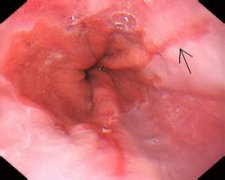

食管炎即食道炎,泛指食管黏膜淺層或深層組織由于受到刺激或損傷,食管黏膜發(fā)生水腫和充血而引發(fā)的炎癥?;瘜W性刺激包括胃酸、膽汁、烈酒以及強酸、強堿、藥物等;物理性刺激包括燙的...